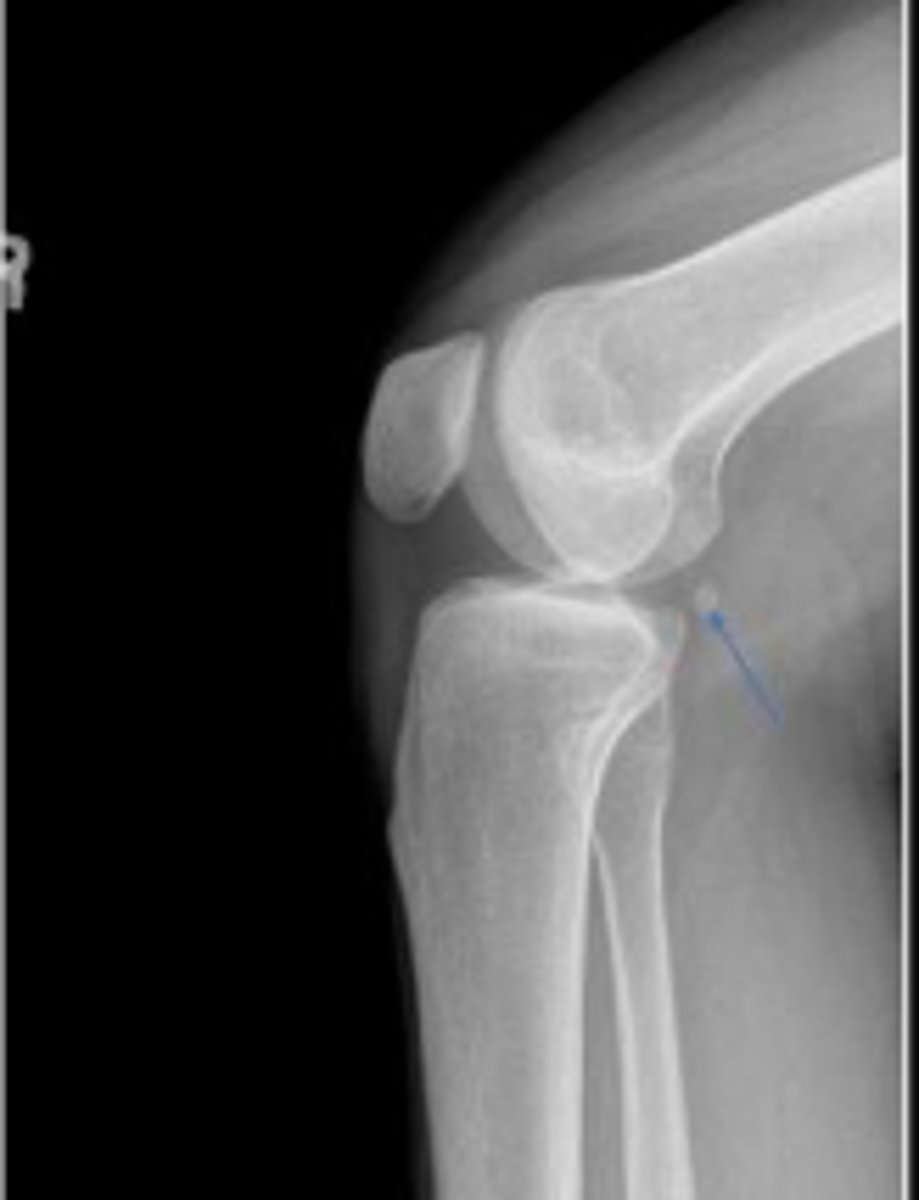

Right AP knee

What is the name of the radiographic view?